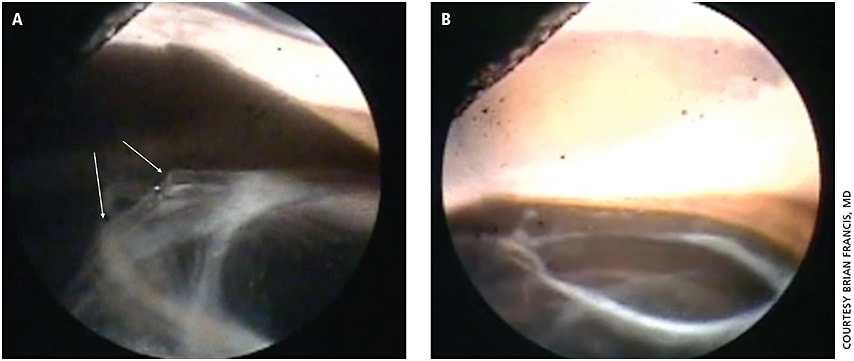

Dr. Francis has used the endoscope when managing patients referred for lingering problems. In one case, a patient presented with uveitis-glaucoma-hyphema syndrome after cataract surgery and a follow-up procedure to cut off a haptic in the sulcus. Using the endoscope, he saw that the capsule had fibrosed underneath the cut-off haptic (Figure 3A), and the optic next to it tilted the IOL at an angle where the sharp edge pointed up toward the iris. He reopened the capsular bag in that area, tucked in the optic and straightened out the lens implant (Figure 3B).